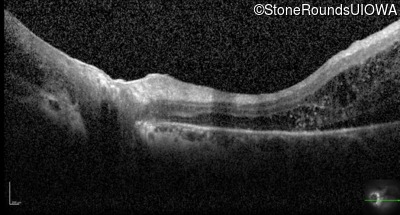

Optical Coherence Tomography - Right - 20/50 +2

Exemplar / OCT Stack